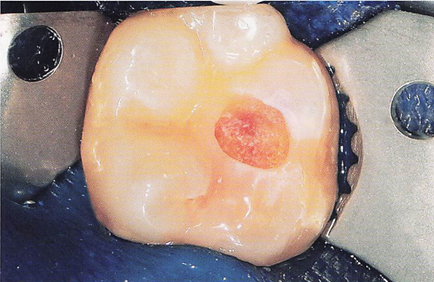

午前-41

23歳の男性。下顎左側第一大臼歯の冷水痛を主訴として来院した。 自発痛はないという。暫間的間接覆髄が行われることになった。水酸化カルシウム製剤貼付前の口腔内写真を別に示す。 この治療法を選択した目的はどれか。2つ選べ。

a.感染歯質の除去

b.歯髄組織の保護

c.軟化象牙質の再石灰化

d.デンティンブリッジ形成促進

解答を見る

b.c